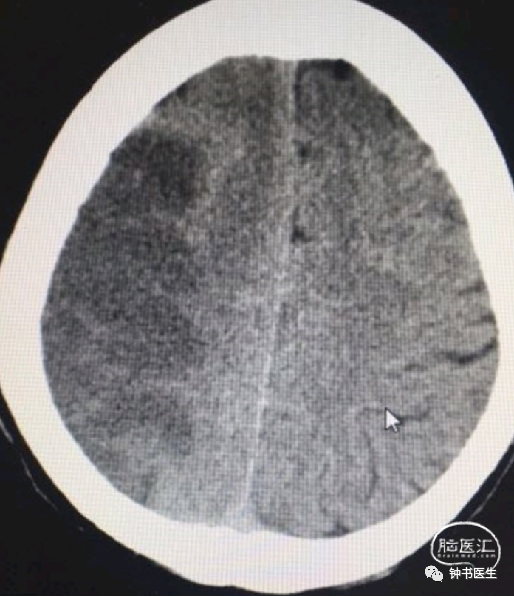

2017-7-6 CT

2017-7-7 CT

2017-7-12 CT